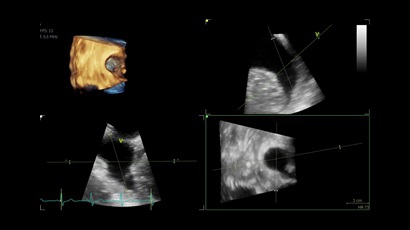

• Vivid IQ 4D с поддержкой технологии объемной реконструкции

• Передовые технологии, такие как 4D чреспищеводная эхокардиография, ЭКГ, стресс-эхо, внутрисердечная ультразвуковая эхокардиография, тканевый доплер и другие.

• Режимы: 4D, 2D (B-режим), цветной допплеровский режим, режим энергетического допплера, M-режим, цветной M-режим, спектральные режимы импульсно-волнового допплера (PW) и непрерывно-волнового допплера (CW), визуализация скорости движения тканей.

• 6VT (биплан/триплан).